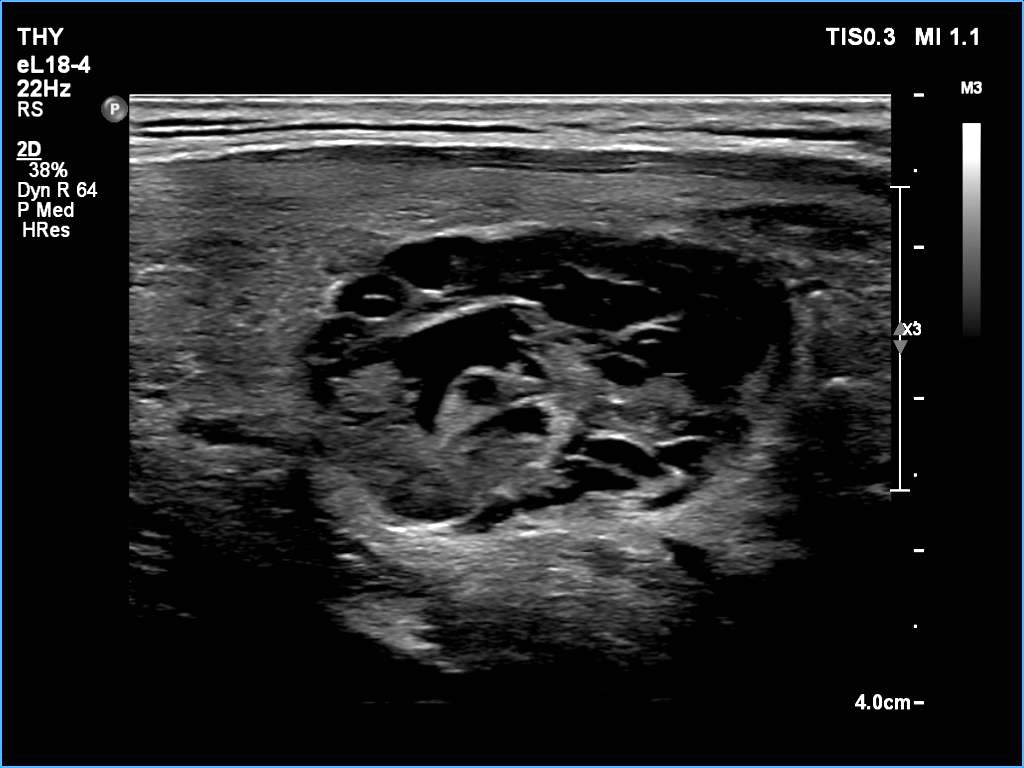

Ultrasonography: The thyroid was echonormal. There was a larger nodular mass in the right lobe which was composed of a dominantly solid echonormal portion that surrounded a dominantly cystic area. There were multiple nodules in the left lobe. The latter included an almost completely cystic lesion.

Comment. The right nodule is dominantly solid one because the cystic portion is less than 50%. The cystic portion of the nodule is multichambered which presents spongiform areas. The left cystic nodule is an almost completely cystic lesion, that has disappeared after the removal of cystic fluid.